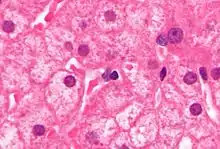

PCR tests have been developed to detect and measure the amount of HBV DNA, called the viral load, in clinical specimens. These tests are used to assess a person's infection status and to monitor treatment.[69] Individuals with high viral loads, characteristically have ground glass hepatocytes on biopsy.